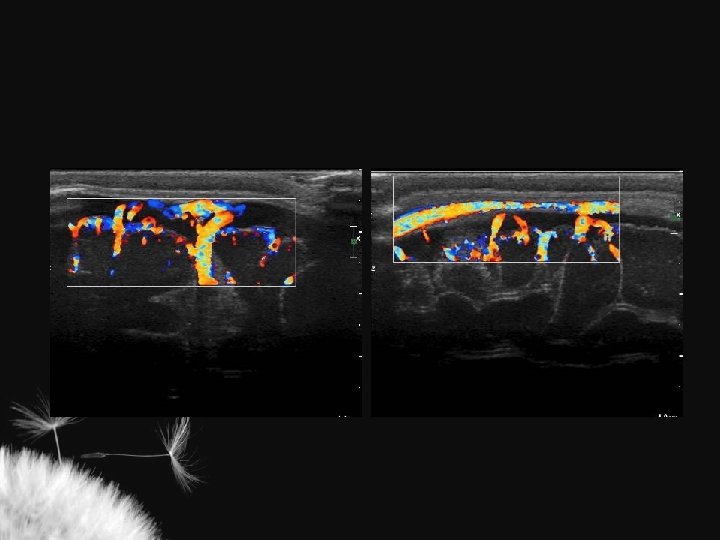

Hidrocefalia benigna da infância – sinal da veia cortical positivo

Coleção subdural – sinal da veia cortical negativo